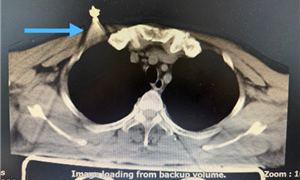

胸骨碎裂直刺心脏边缘!创新术式破解危重胸骨骨折难题

2025.08.20